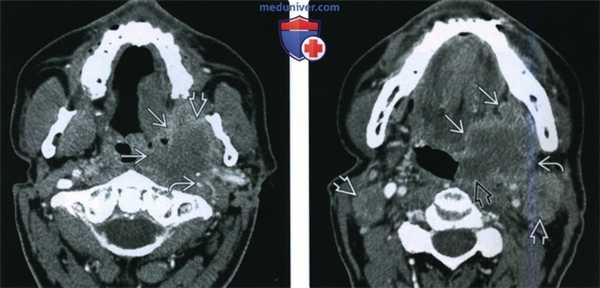

(Слева) При аксиальной КТ с КУ визуализируется объемное образование (инфильтративный ПКР), распространяющееся в жевательное пространство, окружающее и сдавливающее левую внутреннюю сонную артерию, что является признаком стадии Т4b. Был выявлен белок р16 - маркер вирусной инфекции (ВПЧ).

(Справа) При аксиальной КТ с КУ на более каудальном уровне визуализируется опухоль миндалины (ПКР), распространяющаяся кпереди в полость рта, а также вдоль задней стенки ротоглотки до средней линии. Наличие увеличенных и некротически измененных лимфоузлов уровня IIА означает стадию N2c.

(Слева) При аксиальной КТ с КУ у пациента с множественными объемными образованиями шеи справа, курящего и употребляющего алкоголь, определяется увеличение правой небной миндалины, в которой находится объемное образование (T2N2b) размером >2 см, распространяющееся в задние отделы полости рта. Контрольные исследования этому пациенту не выполнялись.

(Справа) При аксиальной КТ с КУ, выполненной этому же пациенту год спустя, определяется выраженное прогрессирование заболевания: стадия опухоли на момент выполнения исследования T4aN2cM1. Опухоль, которая стала гораздо больше, распространяется в полость рта и, скорее всего, в превертебральные ткани. Обратите внимание на двухстороннюю метастатическую лимфаденопатию.